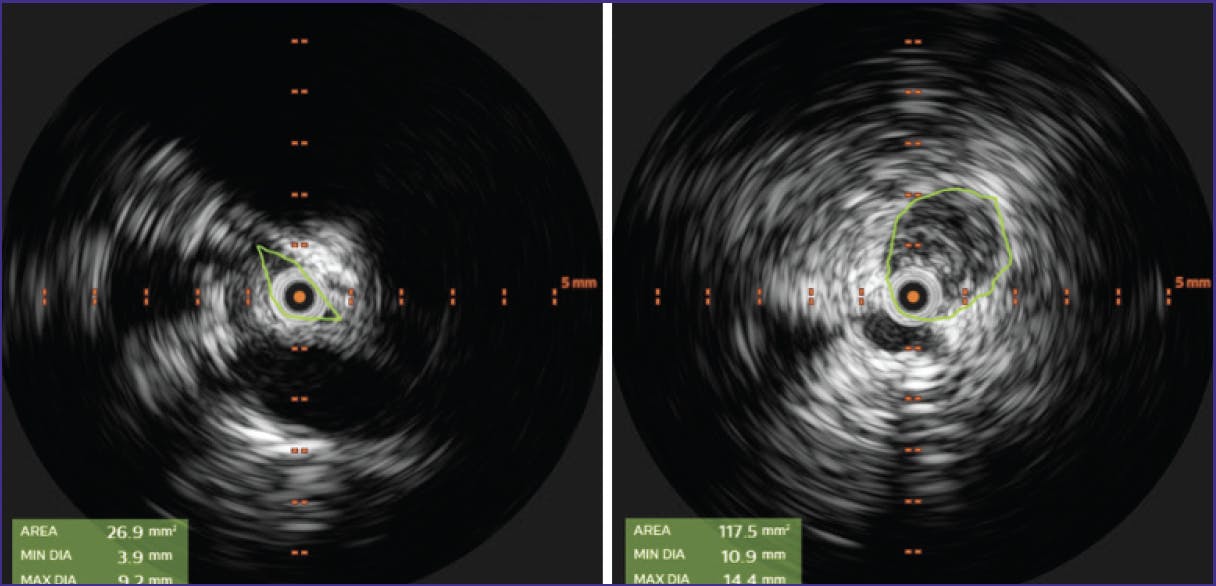

The .035 guidewire was exchanged for a .018 guidewire, and the Pounce™ Venous Thrombectomy System (Surmodics, Inc.) was deployed at the proximal CIV. The system removed acute and chronic thrombus extending from the CIV to the popliteal vein, resulting in restoration of flow (Figure 2). Balloon venoplasty was performed at the May-Thurner stricture in the CIV; however, intravascular ultrasound (IVUS) showed continued stenosis (Figure 3). A 14 X 60 mm Zilver Vena® Venous Self-Expanding Stent (Cook Medical) was deployed at the site of the stricture. Subsequent venography showed occlusive thrombus distal to the new stent (Figure 4). With caution, the Pounce™ Venous System was used to clear the thrombus, and brisk flow was established through the stented CIV (Figure 5).

Figure 2. Thrombectomy with the Pounce™ Venous System removing extensive acute and chronic clot (left). Subsequent restoration of flow (center and right).

Figure 3. IVUS showing continued narrowing at the CIV May-Thurner stricture following venoplasty.